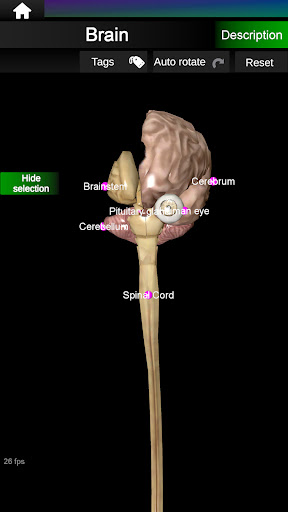

Internal Organs in 3D Anatomy لـ Vodafone Smart N9 Lite

(الأجهزة الداخلية في)

Internal Organs 3D Anatomy 3.4

يمكنك هنا تنزيل ملف حزمة تطبيق أندرويد "Internal Organs 3D Anatomy" الخاصة بجهازVodafone Smart N9 Lite مجانًا، نسخة ملف حزمة تطبيق أندرويد - 3.4 للتحميل على Vodafone Smart N9 Lite اضغط ببساطة على هذا الزر. إنه سهل وآمن. نحن نقدم فقط ملفات حزمة تطبيق أندرويد الأصلية. إذا انتهكت أية مواد موجودة في الموقع حقوقك قم بإبلاغنا من خلال